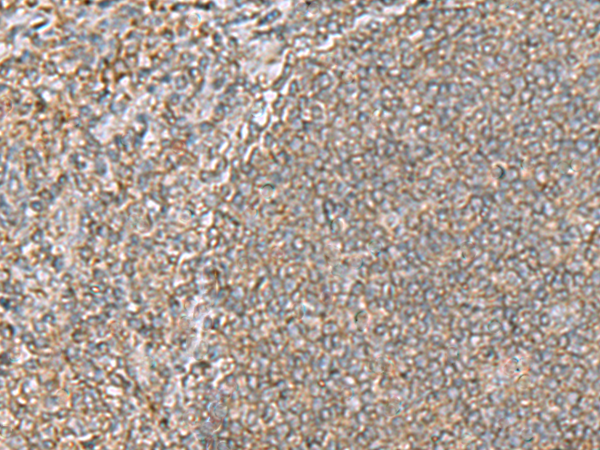

分类: 科研抗体货号: P05754别名: 2410091M23Rik应用: WB,IHC反应种属: Human